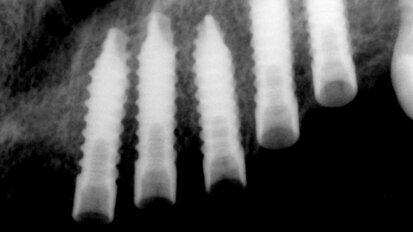

Nepřímá metoda pro ošetřování prostřednictvím provizorií

Týmový přístup při celkové hybridní rekonstrukci.